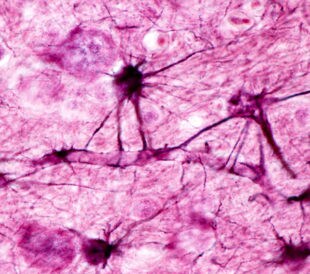

Tuberous sclerosis complex (TSC) derives its name from characteristic brain lesions, or tubers. More than 80% of people diagnosed with TSC have epileptic seizures, and many do not respond to pharmacological treatment, instead requiring surgical tuber resection. While TSC arises from mutations in the TSC genes (TSC1 and TSC2), the underlying molecular events that generate seizures remain elusive.

For this reason, Dombrowski et al. (2014) characterized miRNA expression in cortical tubers derived from TSC patients with epilepsy that does not respond to treatment. They compared expression levels with adjacent non-tuber tissue. They applied quantitative proteomics with tandem mass tags (TMT 10plex, (Thermo Scientific) and an Orbitrap Fusion mass spectrometer equipped with EASY-nLC UHPLC (both Thermo Scientific). In this way, the team evaluated how altered miRNA levels influence protein expression and also examined tumor suppressor p53 and inflammation as potential underlying mechanisms of miRNA regulation in TSC.1 They relied on Proteome Discoverer software (Thermo Scientific) for data processing and searching.